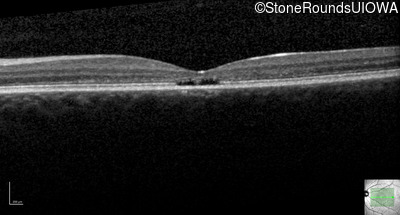

Age at visit: 17 years

OD OS

This 17 year old female first noted problems with her visual acuity around age 13 when she had trouble seeing the projector from the back of the classroom.